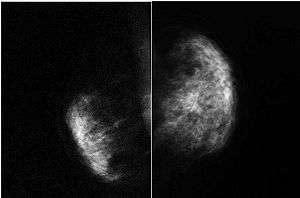

| Digital mammogram (Mediolateral view) showing absence of the pectoralis major muscle and architectural distortion on the left side and normal right breast | |